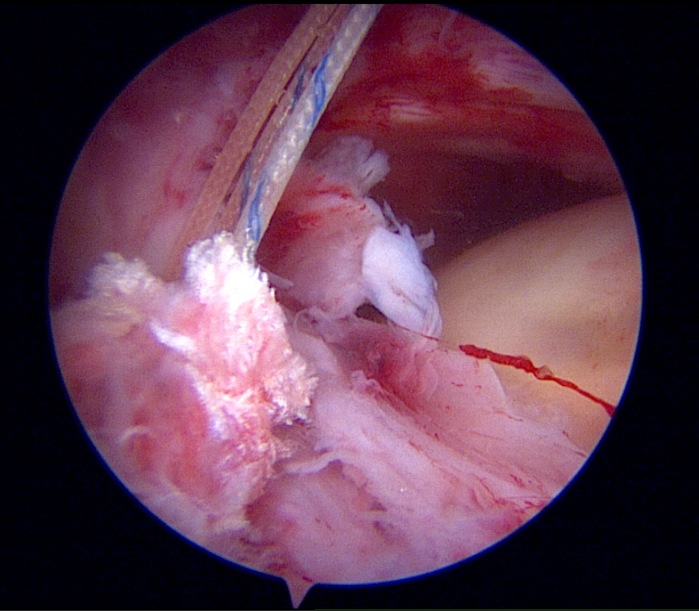

Artroskopi Yardımlı Latissimus Dorsi Tendon Transferi (LDTT)

Masif onarılamaz rotator manşet yırtıklarında (MIRCT) uygulanan latissimus dorsi tendon transferi tekniği. Sırt kasının tendonu omuz bölgesine transfer edilerek kaybedilen omuz fonksiyonu yeniden kazandırılmaktadır.

Artroskopik görüntü — tendon fiksasyonu